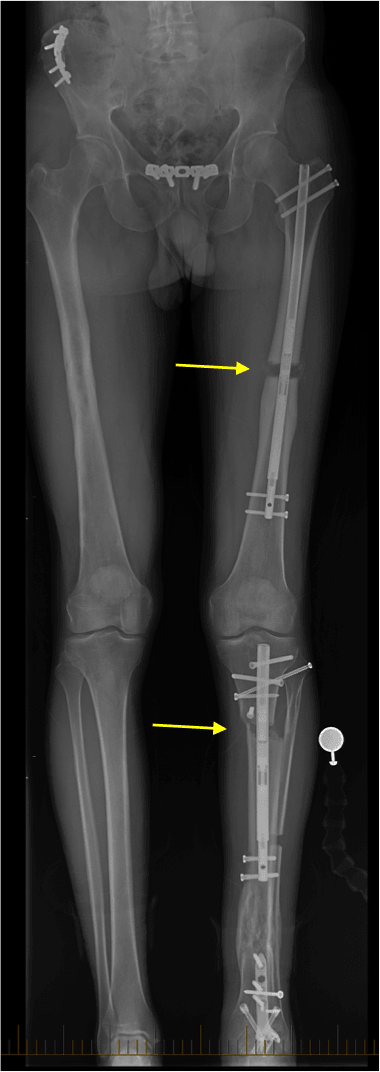

tibial malunion

Clinical photos show a patient who has malunions in his left femur (thighbone) and tibia (shinbone). The malunions involved shortening of his leg by 1.5 inches and rotation. Note how his left leg is turned inward (yellow arrows).

distraction osteogenesis

This x-ray shows the same patient in the side-by-side photos above. His malunions were corrected by rebreaking and realigning the femur and tibia. The internal rotation has been corrected and length has been restored to his shortened leg with internal lengthening rods (yellow arrows).